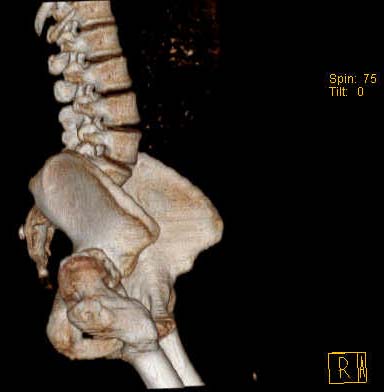

Уважаемые коллеги!Женщина, 35 летВ прошлом по поводу врожденного вывиха бедра перенесла операцию остеотомии по Шанцу

с удлинением правой ноги за счет бедра на уровне диафиза. В последнее время прогрессируют боли в правом тазобедренном суставе, порочное положение правой ноги, затруднена ходьба.Вопросы:1) Целесообразно ли эндопротезирование правого тазобедренного сустава?2) Целесообразный ли следующие действия: канал бедренной кости предполагаем вскрыть для введения ножки протеза на высоте угловой деформации, предполагаем низведение большого вертела с мышцами; протез будет подобран индивидуально, предполагается умеренная версия?В приложении рентгенограммы и трехмерная КТ.В цветном и более качественном варианте КТ размещена здесь

2. К сожалению, техника операции, представленная коллегами из Москвы здесь не получится, т.к. остеотомия бедренной кости была выполнена достаточно низко (по отношению к области сустава). На мой взгляд, целесообразно выполнить остеотомию на высоте деформации с основанием клина кнутри (что бы не было дефекта кости)и ввести понопокрытую ножку с проксимальной и дистальной фиксацией (по типу AML, ее длина 180 мм, при необходимости можно и 200 мм, надо рассчитать). Стабильность ножки будет обеспечена дистальной ее фиксацией, если будут сомнения относительно прочности фиксации короткого проксимального фрагмента, то линию остеотомии можно перекрыть кортикальными аллографтами.

Я думаю что никто не имеет большого опыта в исполнении этих операций, мы все учимся друг у друга, поэтому я представлю ход своих размышлений, основывающихся так же на небольшом личном опыте 4-х операций. Сложности заключаются в том, что по компьютеру трудно представить истинные размеры и сложно "поиграться" с шаблонами. Но изначальная ориентировка на полнопокрытую ножку (или почти полнопрокрытую)шариками (паракоут) длиной 180 (AML) или 200 мм - Zimmer. В последнем случае нужна аксиальная ретгенограмма, дабы избежать перфорации передней стенки бедренной кости. Я наблюдал несколько пациентов с использования ножек с покрытием шариками с фиксацией в бедренной кости на ограниченном участке протяженностью 6-8 см с хорошими результатами, поэтому у меня есть определенный положительный настрой на эти ножки,